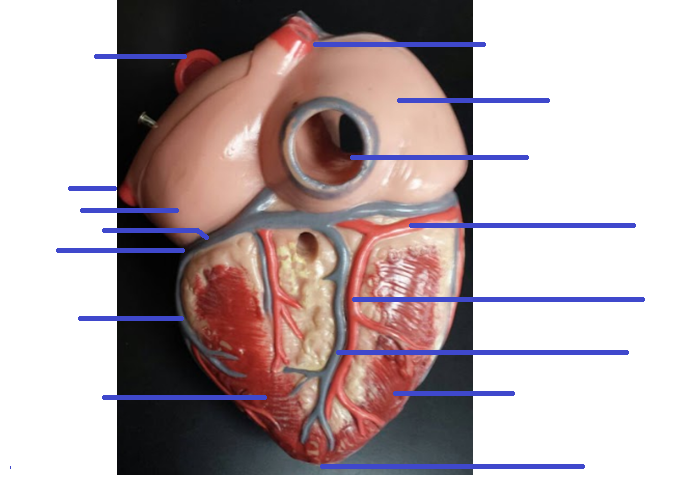

Name the missing parts.

Heart external posterior view